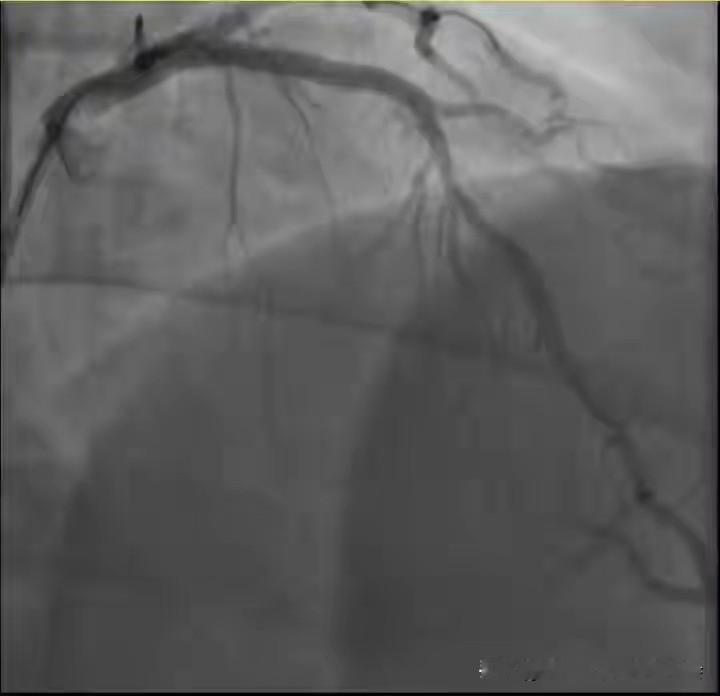

2026年1月初,两位38岁宝爸在运动后突发急性心梗被送医。专家指出,剧烈运动可能通过血压骤升、血液变稠和交感兴奋三种机制,诱发不稳定斑块破裂,导致心梗。 高风险人群包括:有冠心病家族史、三高、肥胖、长期吸烟压力大者,以及“阳康”后人群。病毒可能潜在损伤心肌或加速动脉硬化。 科学预防需做到:运动前进行心血管风险评估;遵循“循序渐进”原则,从低强度开始;充分热身与恢复;避免在极端天气和疲劳状态下剧烈运动。出现胸闷、胸痛等信号立即停止并就医。 运动是健康良药,但必须科学安全。中年不是健康保险箱,真正的健康智慧在于懂得如何安全地运动,特别是运动前专业评估对高风险人群至关重要。心梗 心梗症状 心梗风险 老人心梗 心梗预防方法 心肌猝死 心梗前兆 心源性猝死 阳康后运动导致心肌炎是真的吗? 哪些人容易发生心肌损伤? 为什么青壮年易患上心肌炎? 为什么心肌梗死与天气寒冷有关? 心肌梗塞什么原因引起的 诱发心肌梗死的因素有哪些? 为啥年轻的心肌梗死患者越来越多?